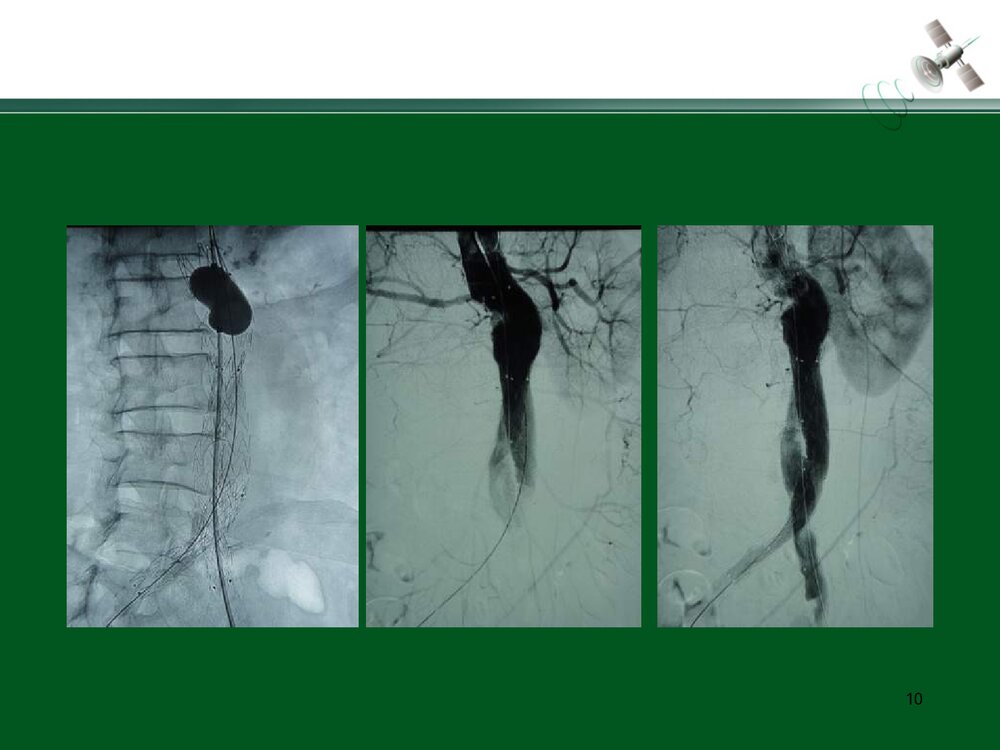

复杂腹主动脉瘤的腔内治疗常光其王深明教育部国家重点学科卫计委国家临床重点专科中山大学附属第一医院血管外科中山大学血管外科研究中心1复杂瘤颈AAA的腔内治疗复杂瘤颈指下列情况1.瘤颈长度小于15mm;2.瘤颈角度大于60度;3.瘤颈直径过大或过小(小于18mm或大于32mm)例1:短瘤颈AAA的EVAR3456例2:短瘤颈伴入路血管狭窄AAA的EVAR7891011例3:瘤颈狭窄且成角大于60度AAA的EVAR12131415161718192021例4:瘤颈成角大于60度AAA的EVAR2223242526例5:瘤颈成角伴腹主动脉分叉狭窄AAA的EVAR272829303132复杂入路AAA的腔内治疗复杂入路是指下列情况:(1)髂动脉弯曲成角超过90°;(2)双侧髂股动脉广泛钙化伴严重狭窄,直径小于7mm;(3)双侧髂股动脉闭塞例6:入路血管严重狭窄AAA的EVAR34353637383940例7:入路血管严重...